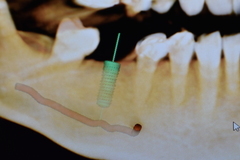

①レントゲン撮影(CT撮影)を行い、術前に正確な診断をします。

③インプラントを入れる方向、位置、距離を測定します。

↑赤い線が耳から顎にかけて流れている血管、神経

④インプラント治療をする箇所のシュミレーションをしていきます。